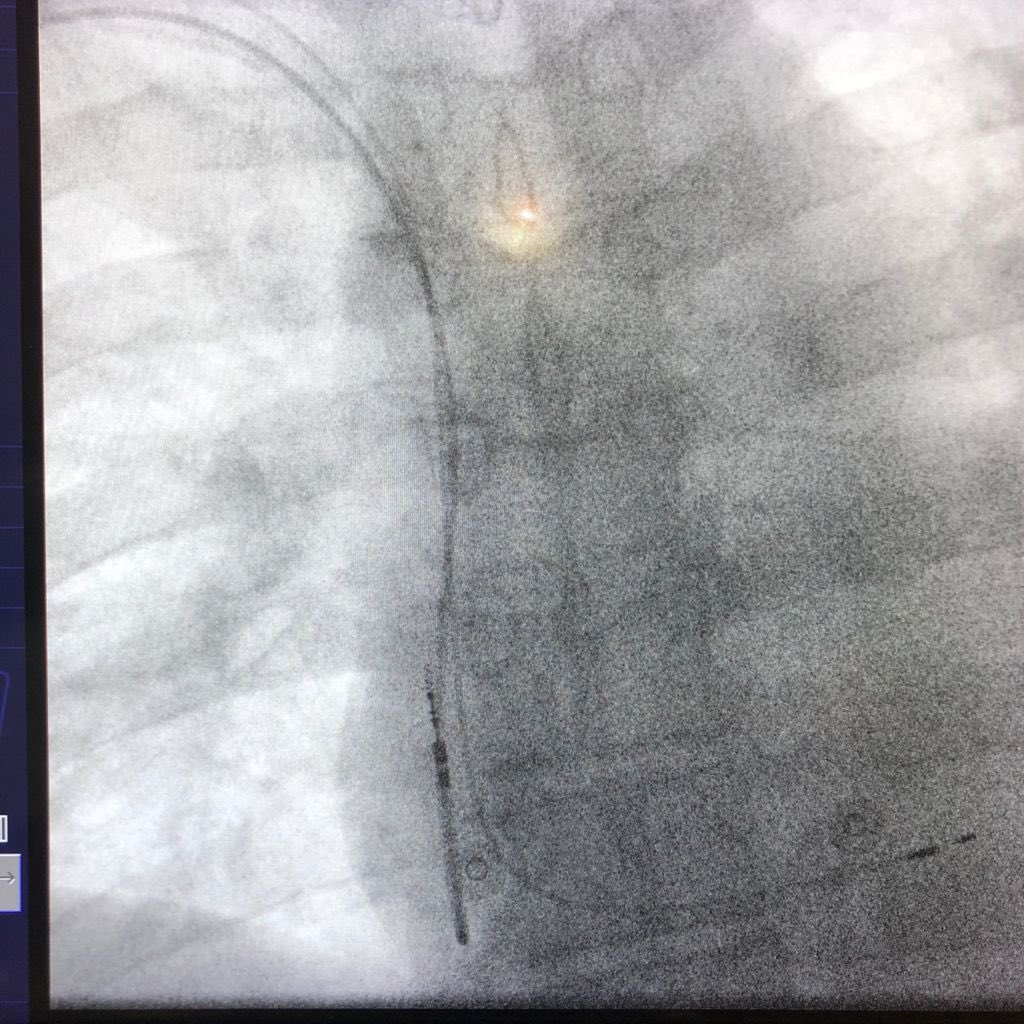

Confirming lead position before the septal perforation #Leftbundlepacing